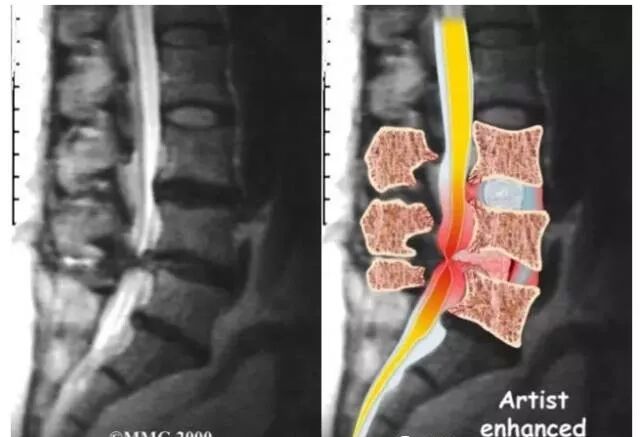

(2)CT,CTM及MRI检查:CT检查可显示椎管及根管断面形态,但不易了解狭窄全貌;CTM除可了解骨性结构外,尚可明确硬膜囊受压情况,目前应用较多,此外,MRI检查更可显示腰椎椎管的全貌,目前大多数骨科医师已将其作为常规进行检查。

(1)间盘突出:当间盘突出时,突出的间盘会占用管腔的位置,从而导致椎管狭窄。

(2)黄韧带、后纵韧带肥厚:当脊柱出现退化不稳定时,黄韧带及后纵韧带受到的应力增高,常常会导致其变性或断裂,而长期的损伤、修复过程必然使黄韧带、后纵韧带增厚,那么椎管官腔的空间就会变小,从而导致椎管狭窄。